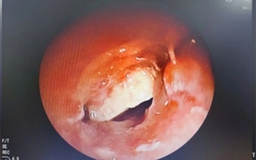

Ho, khó thở hơn một năm đi khám phát hiện dị vật ở phế quản